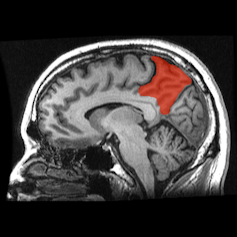

En utilisant cette approche, des expérimentations ont montré que le passage d’un sommeil REM non lucide à lucide était associé à une activité accrue des zones frontales du cerveau. De façon significative, ces aires sont associées à des fonctions cognitives « supérieures » comme le raisonnement logique et le comportement volontaire qui sont classiquement observés uniquement en état d’éveil. Le type d’activité cérébrale enregistrée, des ondes gamma, est connu pour signaler différents aspects de l’expérience humaine ; les sensations, émotions, pensées et mémoires sont “liées” ensemble dans la perception d’une conscience intégrée. Une étude de suivi a indiqué qu’une stimulation électrique de ces zones provoquait une augmentation du degré de lucidité vécu pendant un rêve.

Une autre étude a plus spécialement examiné les régions du cerveau impliquées dans les rêves lucides, et a montré une activité accrue dans des régions comme le cortex préfrontal et le précunéus (face interne du lobe pariétal, dans le cortex). Ces zones sont associées, là encore, à des savoir-faire cognitifs dits supérieurs comme le traitement des pensées autoréférentielles, faisant supposer que le rêve lucide est un stade hybride de la conscience.